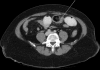

Bowel obstruction is a known complication of Roux-en-Y gastric bypass. It can be caused by adhesions, internal hernia, incarcerated ventral hernia, or intussusception. Sometimes the underlying cause may be unusual. These 2 case reports describe patients who underwent laparoscopic Roux-en-Y gastric bypass and whose postoperative courses were complicated by small-bowel obstruction due to phytobezoars in the ileum, distal to the jejunojejunal anastomosis. We reviewed the literature by using PubMed and Medline for causes, pathogenesis, classifications, diagnosis, and management.